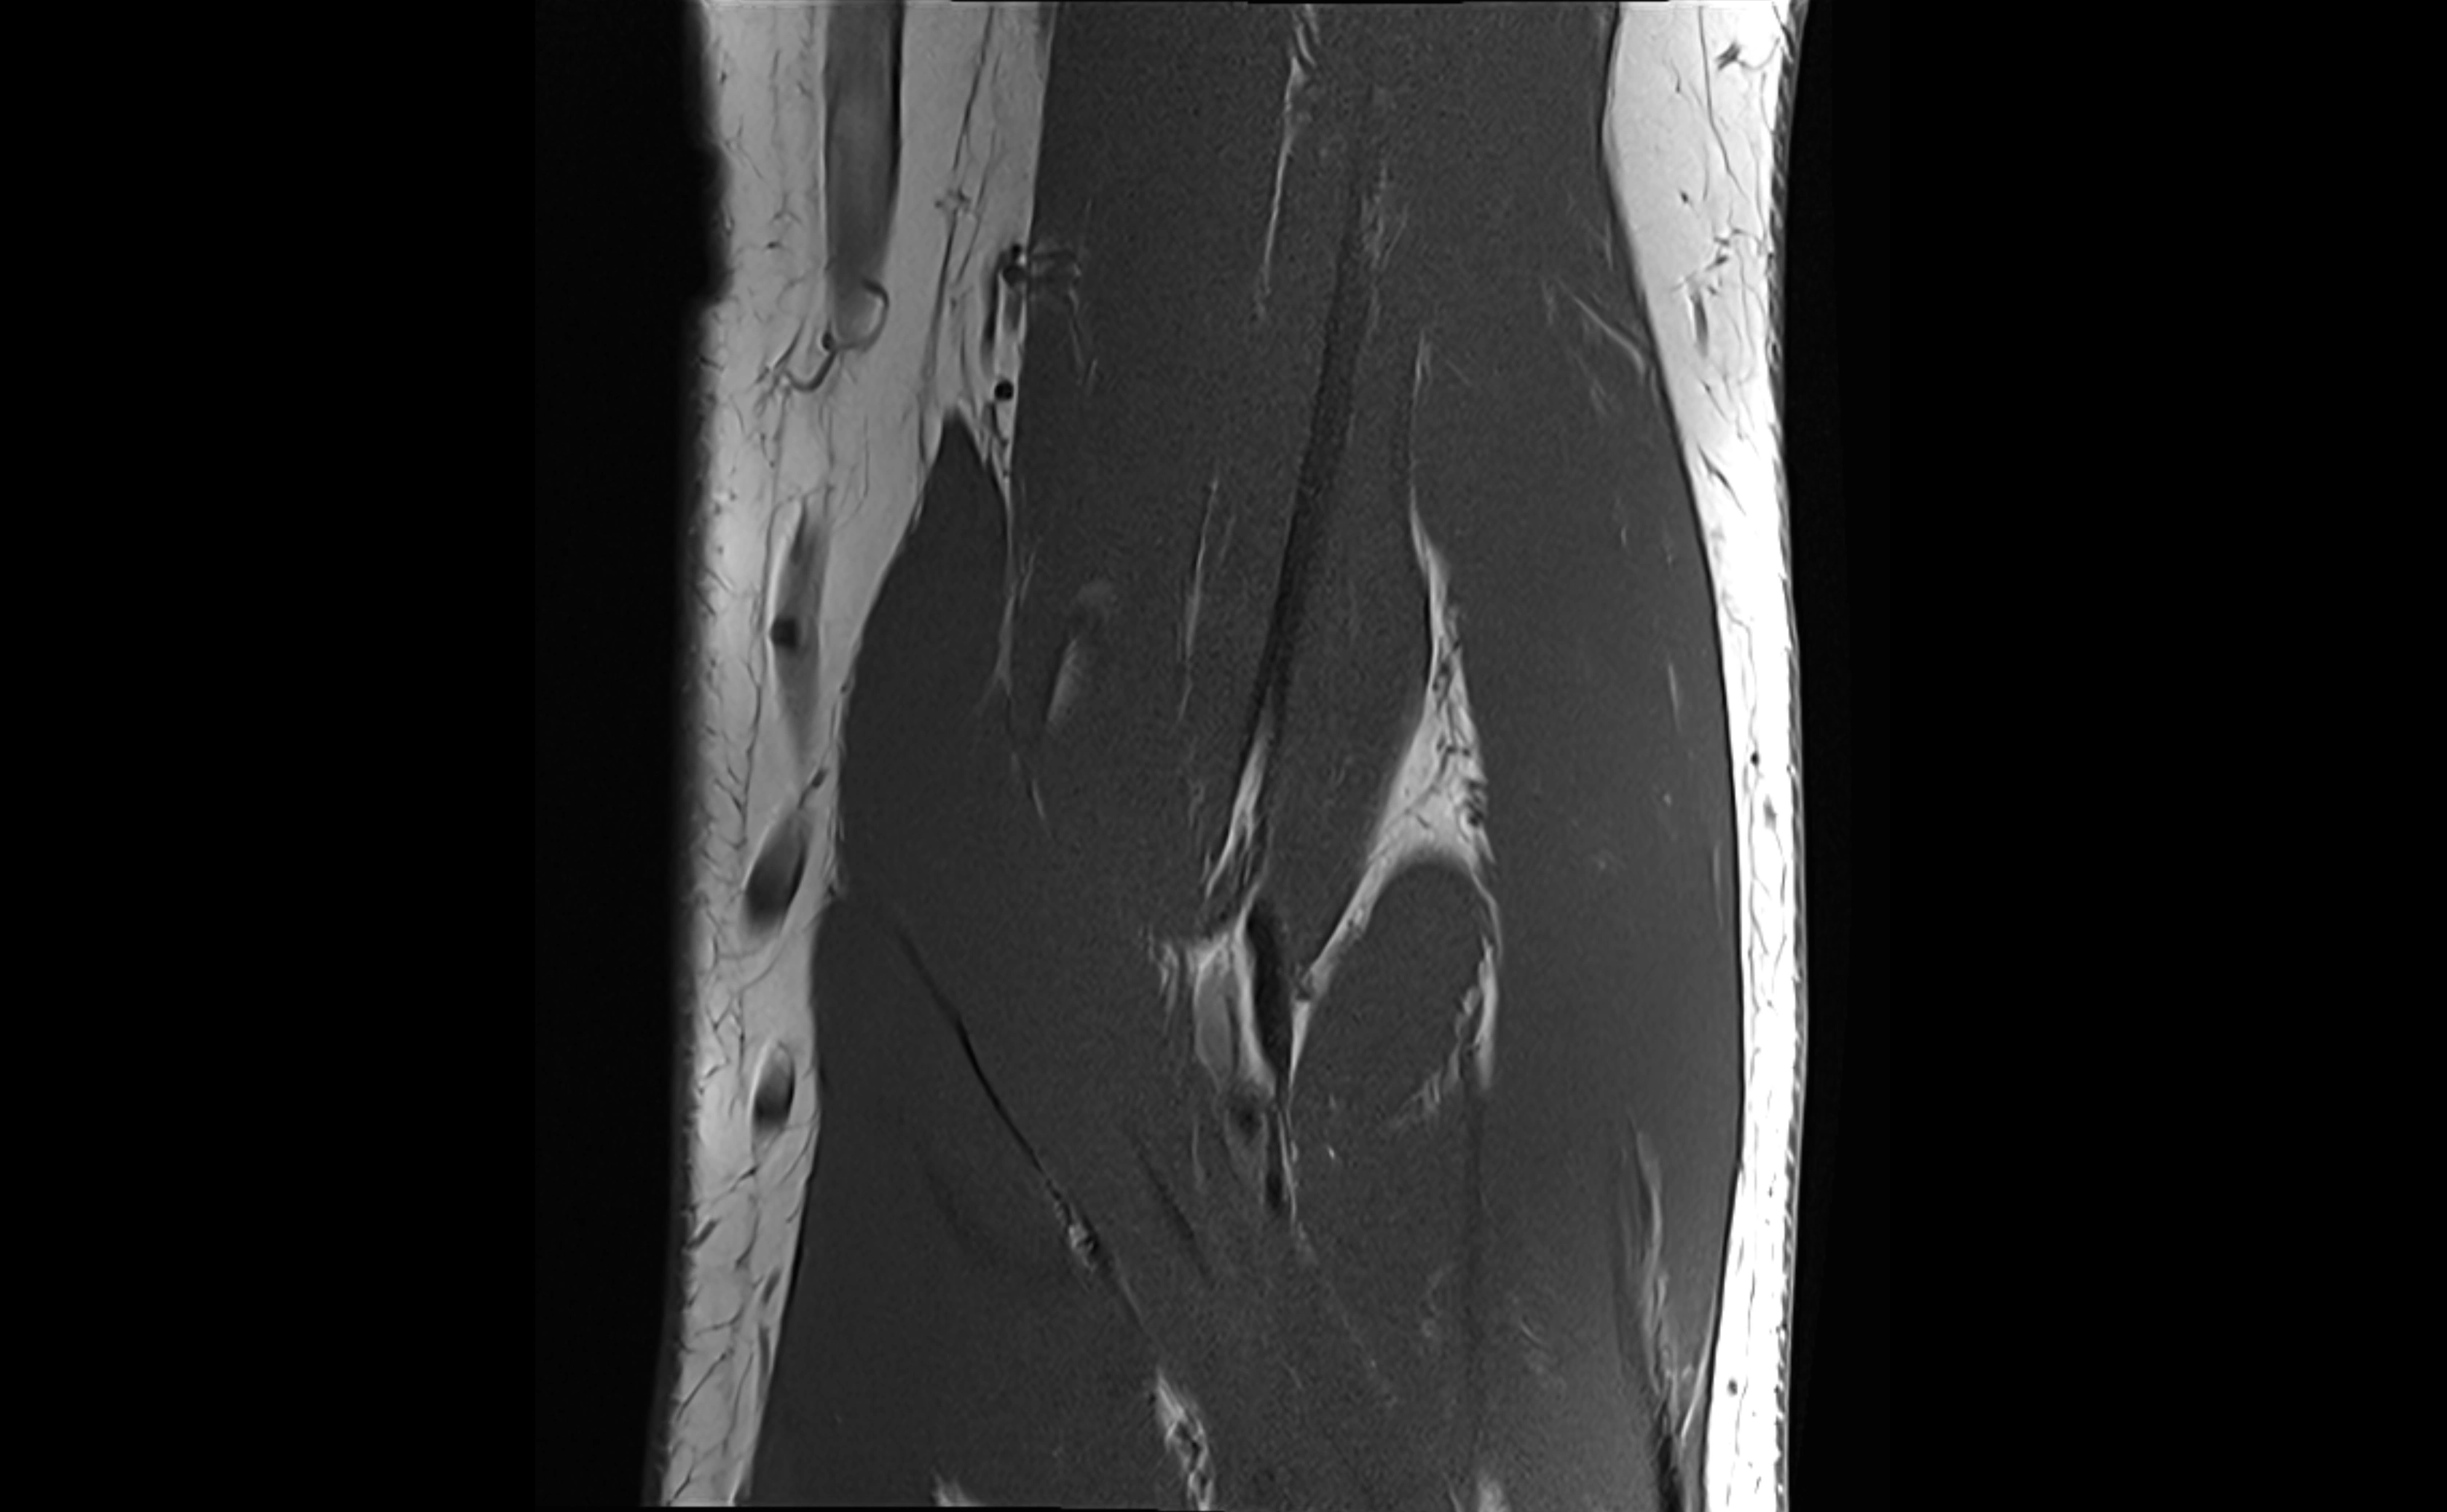

MRI images

image